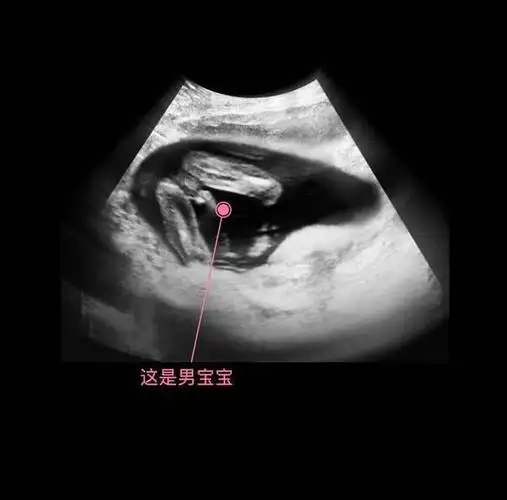

胎儿从卵泡到孕17周,17张图片清晰诠释,男宝女宝看得很清楚